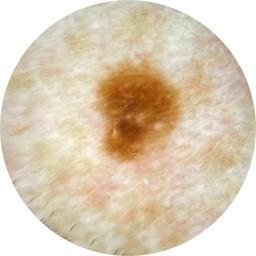

MEL-SELF - Dermoscopic

- Name: MEL-SELF - Dermoscopic

Dermoscopic lesion images (close-up views of benign and malignant lesions) from the MEL-SELF trial (the Melanoma Self Surveillance trial).